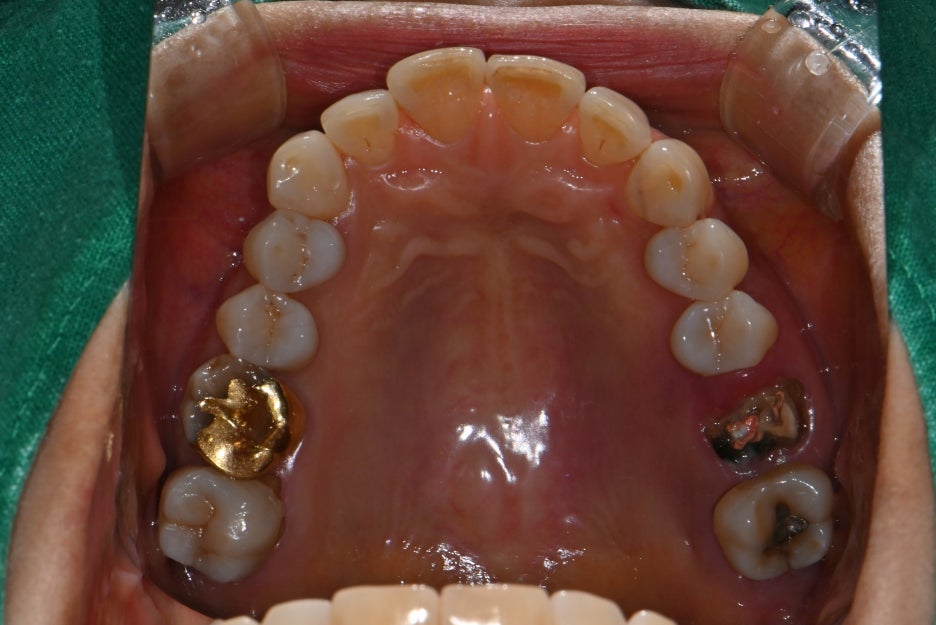

Based on the panoramic X-ray and intraoral photos,

we diagnosed the following:

The two upper left molars were fractured and missing

The surrounding alveolar bone was relatively healthy, so implant placement was possible with minimal bone grafting

Before and after treatment photos